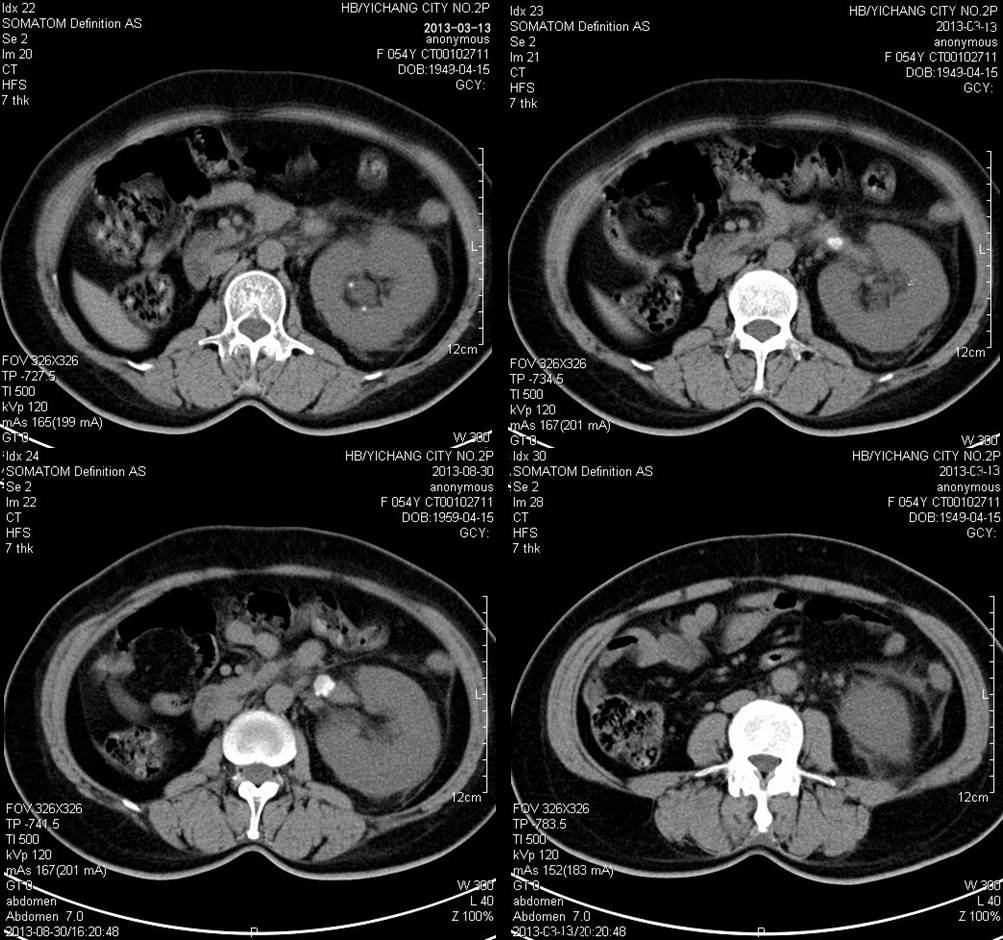

肾脓肿